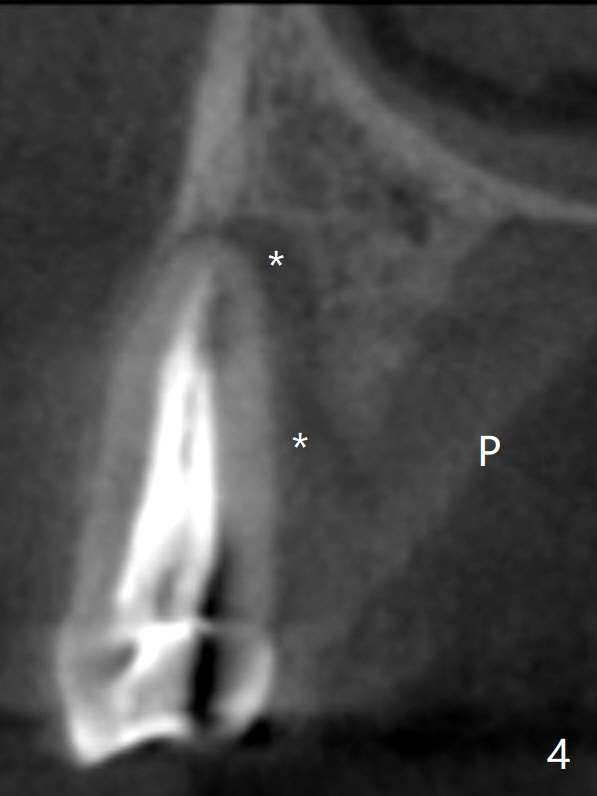

Nine months post apicoectomy of the tooth #4 of a 40-year-old man (Fig.1 <), the root has vertical fracture (Fig.2). It appears that the patient is a bruxer. Place an implant as long as 18 mm (bone level, Fig.3). Start osteotomy in the middle of socket, since there is bone resorption both buccally (apicoectomy) and palately (Fig.4 *). The implant should occupy the meisodistal space for primary stability. Measure root dimension post extraction to determine the implant diameter. Use a 3.8 mm dummy implant.